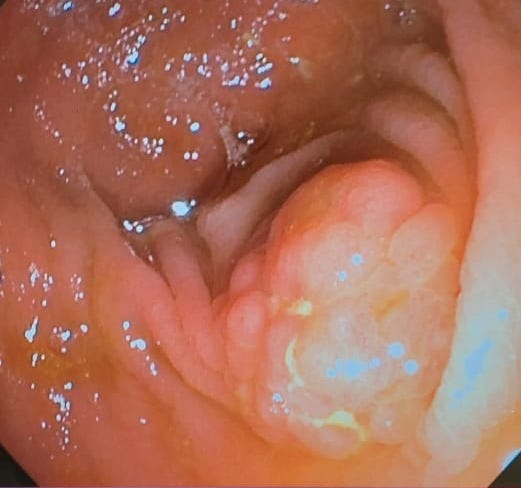

Case 5: A Puzzling Duodenum - Ischemia vs. Inflammation

Case Summary: Images of a duodenum with white-topped folds sparked a differential diagnosis discussion.

Key Teaching Points:

•Ischemia as a Possibility: The white tops of the folds raised suspicion for ischemia, a less common but important consideration.

•Inflammatory Differentials: Other possibilities discussed included chronic duodenitis with atrophic tissue or lymphangiectasia.

•Biopsy is Key: The discussion underscored that biopsy is essential to differentiate between these possibilities and make a definitive diagnosis.